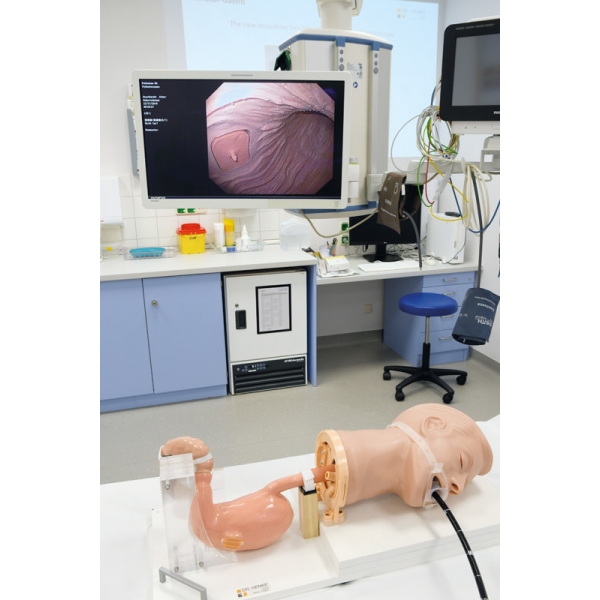

Simulator Gastro združuje možnosti realističnega anatomskega modela in usposabljanja za intervencijsko endoskopijo. Veliko število različnih vložkov omogoča zdravljenje polipov, kot so vbrizgavanje, dvigovanje, rezanje in odstranjevanje, simulacija zaustavitve krvavitve, stentiranje in drugo. Simulator in vložki so izdelani iz popolnoma umetnega materiala.

- Model za usposabljanje za intervencijsko gastroskopijo

- Realistične anatomske strukture

- Vadba z obstoječimi endoskopi in originalnimi pripomočki